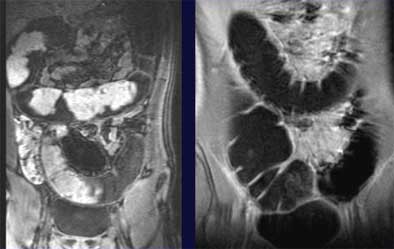

Image analysis showed that fecal tagging was optimal in all patients, and residual air did not cause any significant artifacts, Paolantonio said. Patient tolerance for the exam was high, and the final diagnosis was ulcerative colitis in seven patients and Crohn's disease in three patients. Unprepped MR colonography was able to define the thickening of the colonic wall and the extension of the inflammation following gadolinium injection.

"In the three patients with ulcerative colitis we observed a diffuse involvement of the entire colon from the sigmoid to the descending colon and the colonic wall was thickened and we observed stratification," he said. "In seven patients affected by Crohn's disease, the thickening was more focal."

| Unprepped MRC technique shows wall-thickening patterns in patient with ulcerative colitis, left, and another patient with Crohn's disease, right. Images courtesy of Dr. Pasquale Paolantonio. |